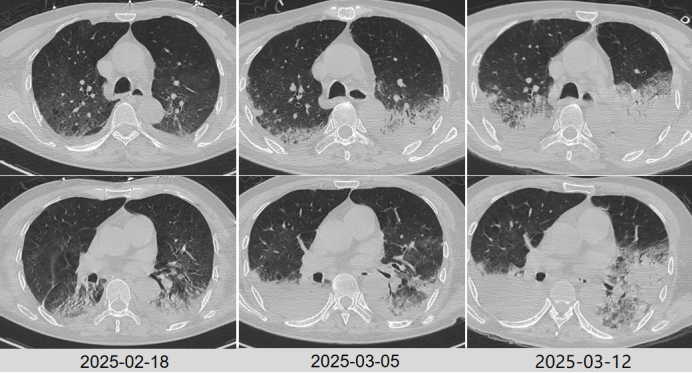

根据病原学结果,先后予以米卡芬净+美罗培南、哌拉西林他唑巴坦+环丙沙星头孢他啶阿维巴坦抗感染治疗2025324日拔管3月27日复查胸部CT提示肺部病变好转吸收(图5)。患者仍有明显咳痰困难,乏力,四肢肌力下降,经康复锻炼恢复欠佳

图片

5  复查胸部CT对比

2025年4月16日复查胸部CT明显进展(图7)。调整头孢哌酮舒巴坦为美罗培南+莫西沙星抗感染,无创呼吸机辅助通气,入重症康复科ICU。

7  患者胸部CT较前变化